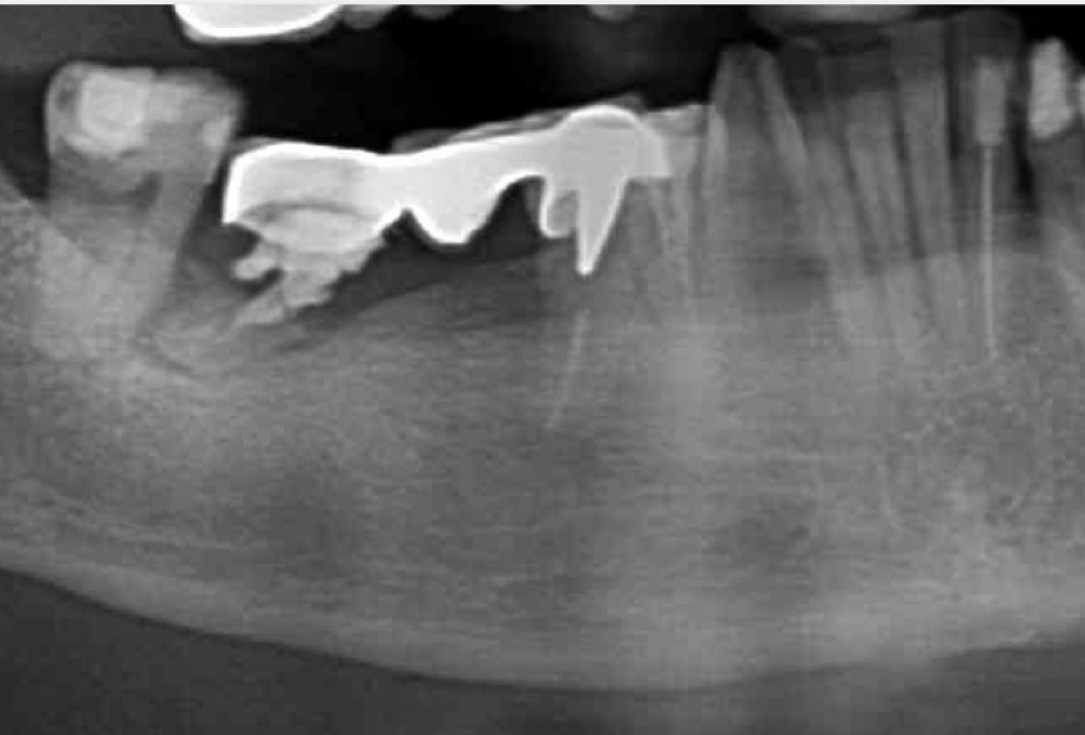

1/9 - X-ray of initial clinical situationPeri-implant soft tissue augmentation for pontic with mucoderm® - Dr. M. Frosecchi